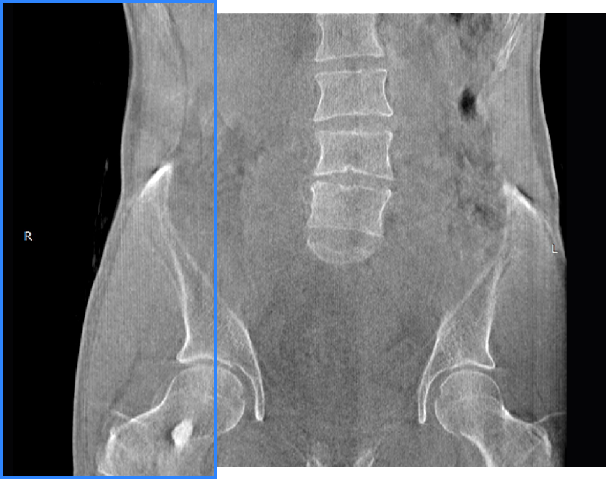

髋关节

精准诊断

手术方案规划

术后随访